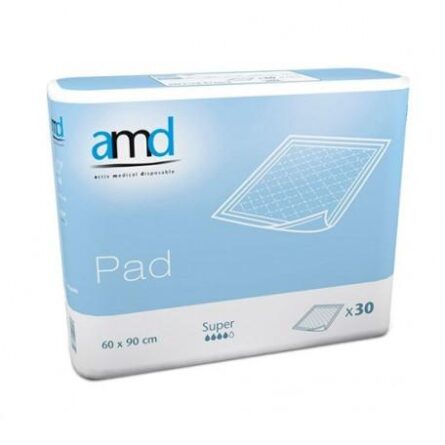

Protector Para Cama Amd Pad Super 90 X 180 20 Unidades

Original price was: $66.31.$55.70Current price is: $55.70.